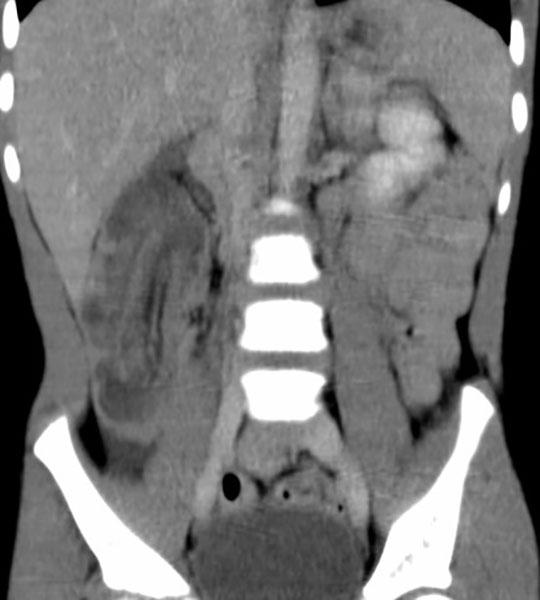

What are diverticula?

Outpouchings (herniations) of the mucosal layer through a weakened muscular layer of the bowel wall.

Where do diverticula most commonly occur?

The sigmoid colon.

At sites where mesenteric vessels penetrate the bowel wall, near the tenia coli.

Do diverticula usually occur singly or in groups?

In groups, not singly.